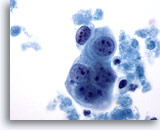

Figure 53

Breast FNA, Colloid carcinoma.

The malignant cells in this lesion are bland, with smooth nuclear margins, evenly distributed chromatin and no visible nucleoli. If the mucin is not noted the cells may be misinterpreted as benign. 60x

Figure 53

Breast FNA, Colloid carcinoma.

The malignant cells in this lesion are bland, with smooth nuclear margins, evenly distributed chromatin and no visible nucleoli. If the mucin is not noted the cells may be misinterpreted as benign.

60x